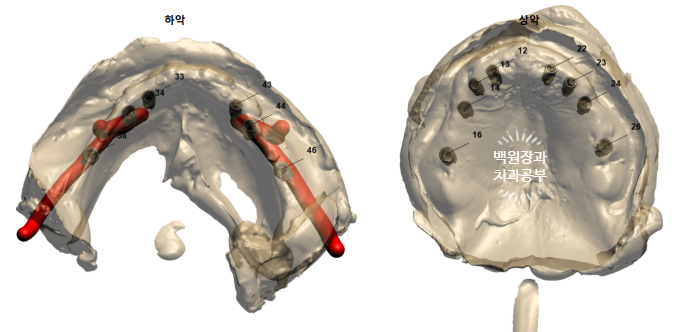

오스템 원가이드 시스템

-> 네비게이션 임플란트 수술을 하기 위한 준비.

임플란트를 많이 심어내는 것도 어렵지만, 치조골 이식술 및 상악동 골이식술이 다량 들어가야 하는 상태로 수술을 하기 전 수술을 도와주기 위한 네비게이션 임플란트 장치를 만들어야 했습니다.

오스템 임플란트의 원가이드 시스템을 이용하는데요, 쉽게 얘기하면 환자분께서 촬영하신 CT 상에서 모의 수술을 진행해보는 것이라 생각하면 됩니다.

오스템 임플란트와 협업으로 진행되는데요, 나중에 만들어질 보철물의 위치를 미리 설정하고 역으로 임플란트 위치를 계산하는 방식입니다.

'하악'이라고 표시되어 있는 왼쪽 사진을 보시면, 빨간색으로 하치조동맥이 표현되어 있어 임플란트 수술 시 신경과 혈관이 다치치 않게 수술할 수 있도록 합니다.

이런 식으로 임플란트를 배열해보는데요, 예시로 든 위치는 오른쪽 위 앞니부위 임플란트입니다.

가운데 사진을 보시면, 나사모양의 임플란트가 겨~우 잇몸뼈 내부에 담기게 심어지는게 예상됨을 아실 수 있죠?

임플란트는 치아랑 달라 주변에 2mm 이상의 건전한 잇몸뼈가 형성되어야 하는데요, 이를 보면 상당히 많은 양의 치조골 이식술이 '성공적으로' 이루어져야겠구나.. 라고 생각할 수 있게 됩니다.

아래턱 임플란트들도 마찬가지로 뼈가 너무 없는 상황이었습니다.

다행히 보시면, 임플란트 하방으로 신경관 손상은 우려되지 않는 상황....

그나마 이게 조금 희망적이네요 ㅠㅠ

아래턱 왼쪽에 비해 오른쪽은 그나마 조금 상황이 좋았습니다.

이런 식으로 오스템임플란트 부서와 협업하여 임플란트 위치를 설정하게 됩니다.